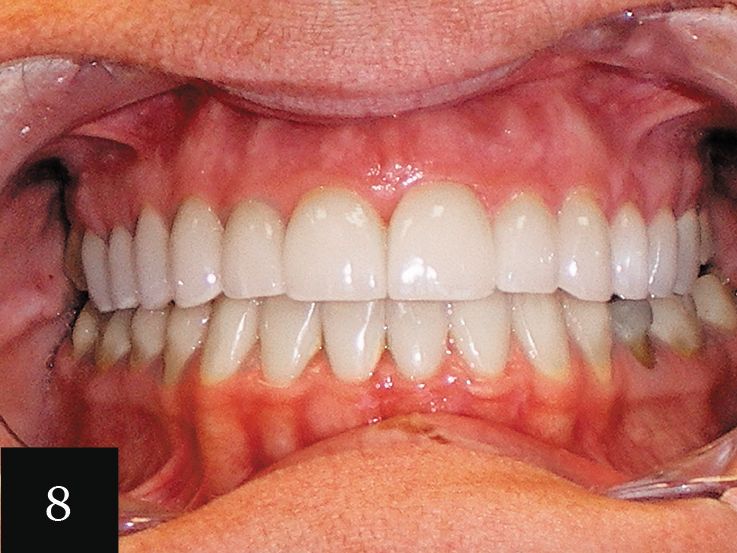

This case showcases a woman in her mid-30s who had an anterior open bite, as well as a history of bulimia (Figs. 5-6). The eating disorder led to severe wear, which can be seen on the upper arch. The gum line was also very irregular. The impression accurately captured the detail of the teeth and a series of 12 aligners was made.

Following this initial phase, an additional impression was taken for six more aligners. Finally, one more impression was taken with Imprint 3 VPS impression material to create crowns for tooth Nos. 3-14. This treatment significantly elevated the patient’s level of confidence in her smile (Figs. 7 and 8).